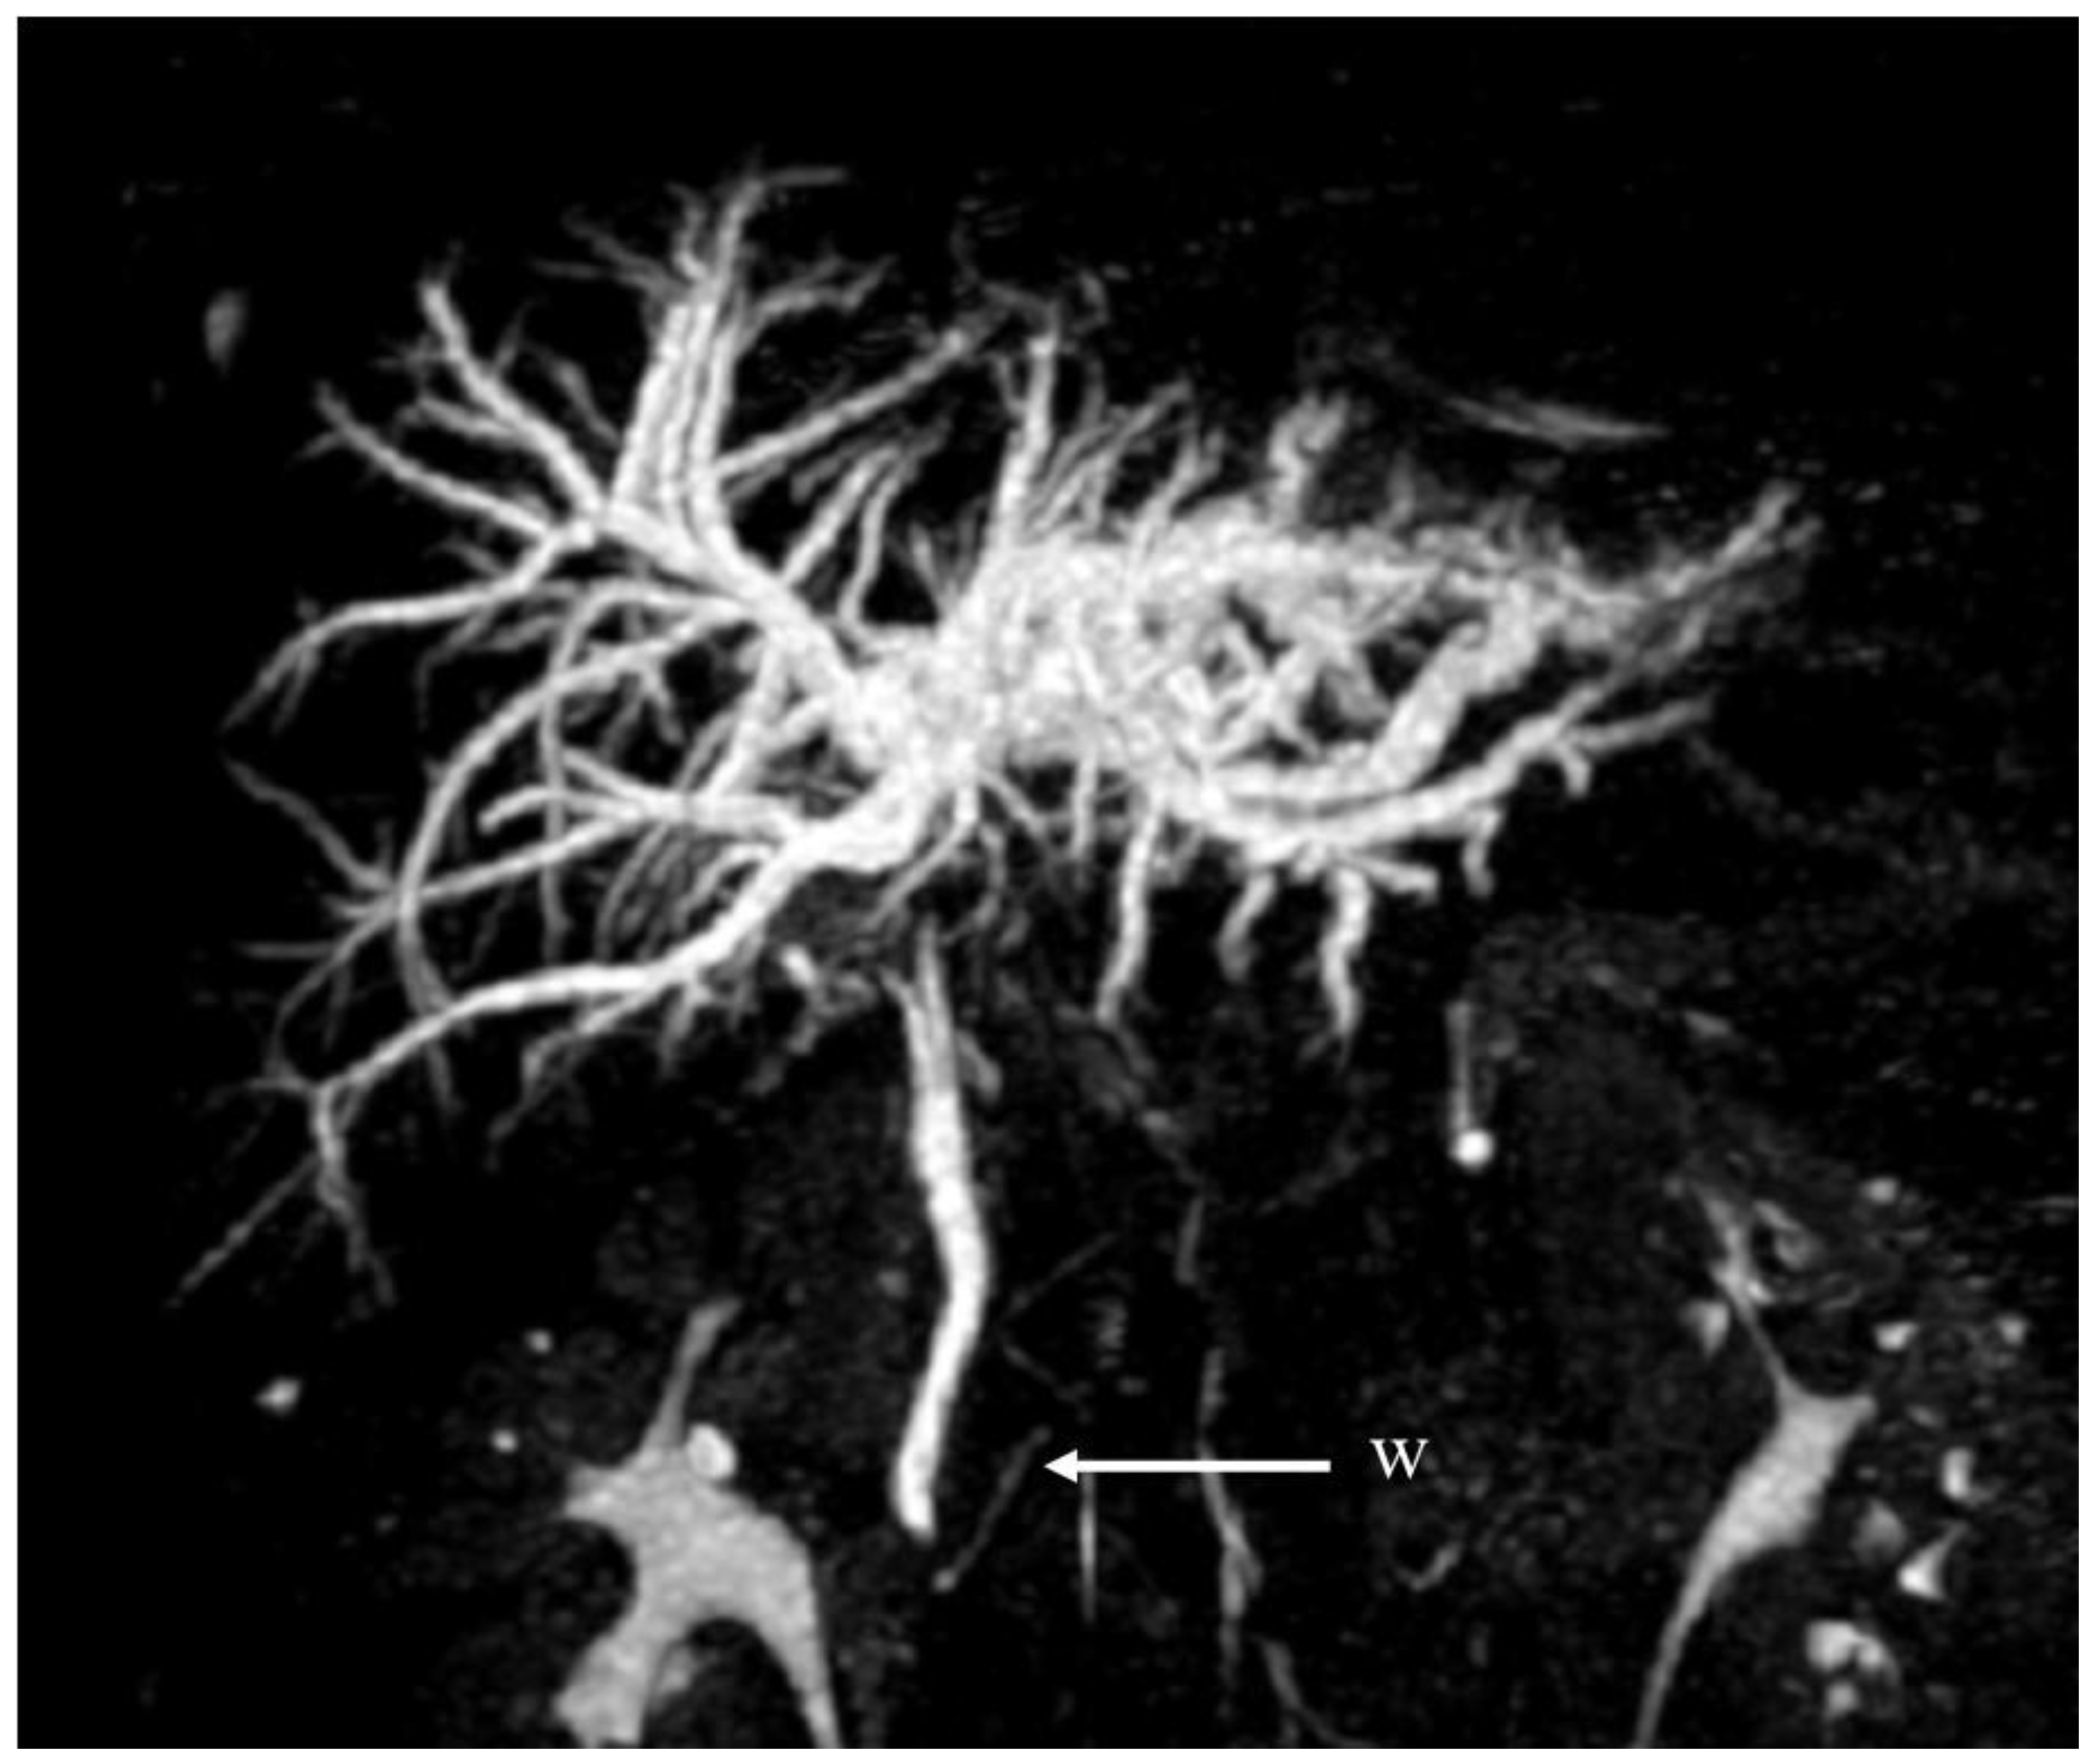

| Appropriate imaging modality and features | MRCP, ERC. Beaded appearance, pruned tree appearance, and band-like stricture. | MRCP. Diffuse or segmental narrowing of the intrahepatic and/or extrahepatic bile duct, associated with the thickening of the bile duct wall. | MRCP. Intraductal calculi and bile duct strictures. | CT-scan, MRI. The CT-scan: lesions with variable c.e., may present as hypovascular with delayed enhancement because of fibrosis. The MRI may produce hypointense on T1 sequences with moderate-to-high hyperintense on T2 sequences. | CT scan (scarce sensitivity for non-calcific stones) and MRCP. | CT scan, MRCP. MRCP most accurate, shows an extrinsic narrowing of the common hepatic duct, a gallstone in the cystic duct, dilation of the intrahepatic and common hepatic ducts, with a normal common bile duct. | CT scan and portal MR and MRCP. Show portal cavernoma, paracholedochal and/or epicholedochal dilations, portosystemic shunts and abnormal morphology of the bile duct. |